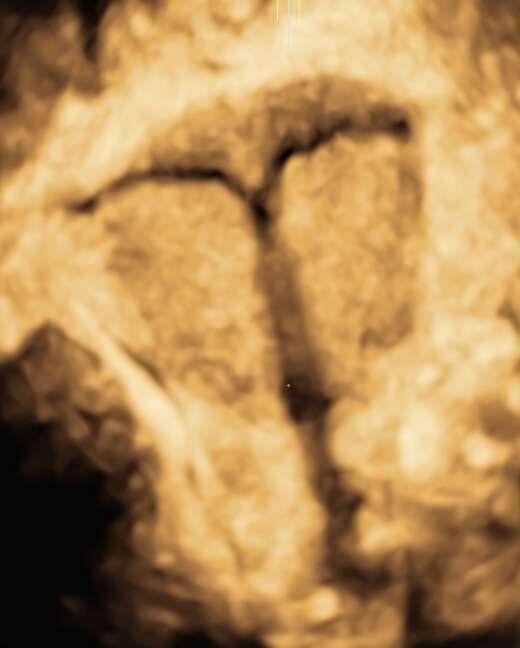

- L'échographie de datation

- Les 3 échographies recommandées pendant la grossesse du 1er, 2ème et 3ème trimestre.

- Les échographies de croissance et/ou de surveillance du col, de contrôle de présentation, sur indication médicale.

- Les échographies de grossesses gémellaires de suivi simple, 1er, 2ème, 3ème trimestre et croissances.